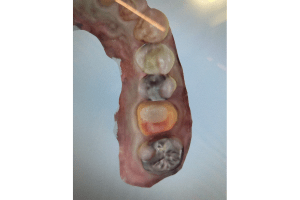

銀歯の中身の写真

麻布十番の歯医者さんで銀歯を外す前の症例写真

こちらは銀歯を外す前と後の写真の比較になります。黒い部分が虫歯になっています。銀歯をつけているとなかなかレントゲンにも虫歯として映ってこないことが多いので、発見が遅れてしまうことがあります。